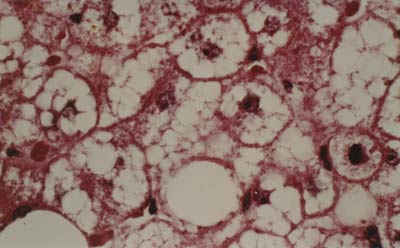

Histologisch bietet die Schwangerschaftsleber

ein normales Bild. Elektronenoptisch finden sich

jedoch bei ca. drei Vierteln der Schwangeren im letzten Trimenon

mitochondriale Veränderungen in Form von Vergrößerungen,

Verformungen und kristallinen Einschlüssen. Es dürfte

sich um adaptive Veränderungen handeln, wahrscheinlich bedingt

durch die erhöhten Steroidhormonspiegel, denen kein Krankheitswert

zukommt und die sich nach der Geburt vollständig zurückbilden

(Abb. 1.1) (69, 70, 74). Eine besondere Ausprägung

erfahren diese strukturellen Alterationen der Mitochondrien im Rahmen

der intrahepatischen Schwangerschaftscholestase (s. Kap. 1.3.1.),

möglicherweise sind sie auch pathogenetisch bedeutsam bei der

akuten Schwangerschaftsfettleber (s. Kap. 1.3.3).

Abb. 1.1 Ausschnitt einer Leberparenchymzelle

bei ungestörter Schwangerschaft 8. Monat. Neben wenigen, normal

strukturierten Mitochondrien finden sich zahlreiche vergrößerte

Mitochondrien mit kristallinen Innenstrukturen und dichtem Cristae-Besatz.

Bis auf eine geringe Vakuolisierung des endoplasmatischen Retikulums

sind die übrigen Zellorganellen normal. Vergr. 13800fach.